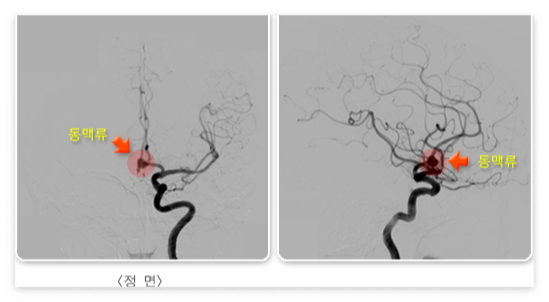

- 거미막밑출혈

뇌 동맥의 한 부분이 꽈리처럼 부풀어 올라 생긴 것을 동맥류라고 합니다. 동맥류 부위는 혈관벽이 약해서 잘 터질 수 있는데, 이 경우 피는 뇌를 싸고 있는 거미막(지주막) 밑에 고이게 된다. 따라서 출혈 발생 초기에 뇌내 조직의 직접 손상은 심하지 않아, 다른 신경학적 증상보다는 심한 두통과 구토가 특징입니다.

3. 혈관조영술

- 혈관조영술이란 X-선을 투과시키지 않는 조영제를 혈관 속으로 주입하고, X-선 사진을 촬영하여 혈관의 영상을 얻는 검사법이다. 우선 가는 카테터(도관)를 경동맥이나 쇄골하정맥, 상완동맥 & 대퇴동맥 등을 통해 삽입하고 촬영을 원하는 혈관 근처까지 전진시킨 후, 도관을 통해 소량씩의 조영제를 주시기로 주입하면서 사진을 촬영한다. 혈관조영술은 혈관을 정확히 볼 수 있는 장점이 있지만, 검사용 장비의 일부가 체내 조직 안으로 들어가는 침습적인 검사법이기도 하다. 뇌혈관 및 혈역학적 상태, 그리고 뇌동맥류의 모양이나 뇌혈관 기형 상태를 정확히 평가하기 위한 진단적인 목적 이외에도, 뇌혈관을 통한 응급혈전제거술 혹은 스텐트 시술을 위한 치료목적으로도 시행한다.

- 거미막밑출혈의 경우, 시간이 지나면서 재출혈이 발생할 위험이 상당히 크므로, 동맥류의 목부분에 클립을 키우는 수술이나, 늘어난 동맥류를 혈관 내 시술로 폐쇄시키는 시술이 필요하다. 그 외 철저한 검사와 함께, 혈압 조절 및 체액유지, 혈관연축을 막기 위한 니모디핀 처방 등을 함께 해야한다.